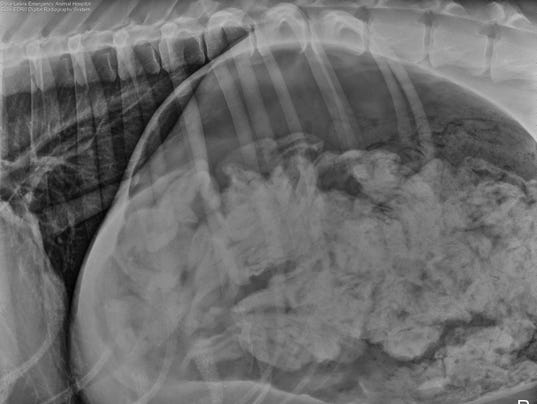

개 위속에서 양말 43켤래 나옴

개주인이 개가 아파서 병원에 데려갔는데 x레이에 이상한게 찍힘

수술하려고 개복하니 양말 43개와 반쪼가리였는데 모양 색깔 다 달랐다고 함

개이름은 Great Dane 이고 세살이라고 함

수술후 괜찮아졌다고 함